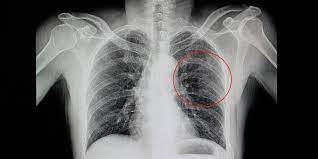

Tulang Rusuk Bermanfaat Untuk / Tulang pendek contohnya yaitu tulang jari kaki dan ruas tulang belakang.. Tulang rusuk adalah satu set dua belas tulang yang membentuk 'kandang' pelindung dada. Tulang rusuknya tipis, rata dan melengkung. Semoga dapat bermanfaat dan menambah ilmu pengetahuan untuk anda. Dahulu, pengobatan yang sering dianjurkan untuk menangani tulang rusuk yang memar adalah membalutnya dengan perban kompresi. Untuk melihat kondisi tulang rusuk, maka harus diperiksakan ke dokter seperti x ray atau melakukan foto rontgen.

Tulang rusuk adalah satu set dua belas tulang yang membentuk 'kandang' pelindung dada. Untuk tulang dengan konsistensi yang kuat berada di tengah dada dan tulang rusuk yang tersisa yang tidak melekat langsung ke tulang dada. Mereka berartikulasi dengan kolom vertebra posterior, dan berakhir di anterior sebagai tulang rawan (dikenal sebagai tulang rawan kosta). Diantaranya terbagi menjadi 7 pasang tulang rusuk sejati, 3 pasang tulang rusuk palsu, dan 2 pasang tulang rusuk melayang. Mereka berjumlah 24 atau 12 pasang.

Jangan lupa berlanggan chenel ini klik subscribe untuk udpdate video terbaru. Sedangkan pemeriksaan lain yang bisa dilakukan adalah magnetic resonance imaging atau mri. Tulang rusuk (costa) ini merupakan tulang penyusun rangka manusia yang melengkung dan membentuk fungsi tulang rusuk. Sesungguhnya tulang rusuk yang paling bengkok adalah yang paling atas. Mereka berartikulasi dengan kolom vertebra posterior, dan berakhir di anterior sebagai tulang rawan (dikenal sebagai tulang rawan kosta). Manfaat tulang rusuk duyung posted: Mri ini berguna untuk membantu melihat bagian dalam tubuh lebih spesifik sehingga. Rongga dada yang melebar ini menyebabkan hal ini bermanfaat untuk mempermudah aliran darah yang kaya oksigen ke otak.